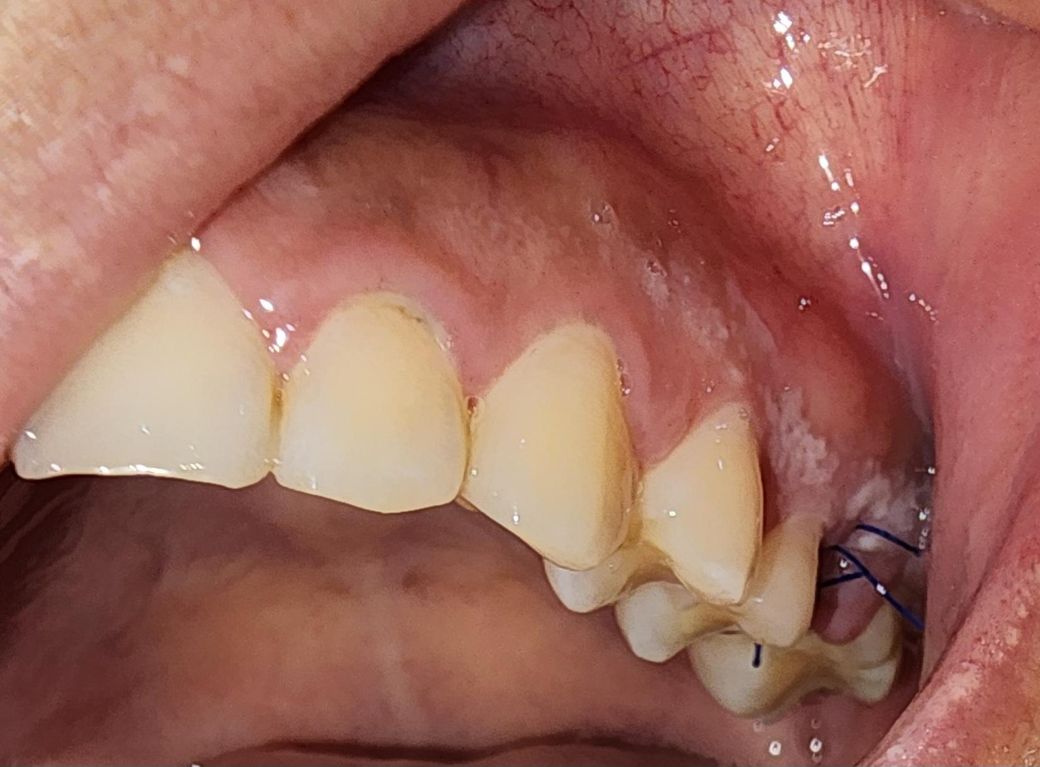

잇몸에 하얀껍질? 같은 게 생겼는데 이게 뭔가요?

뼈이식이랑 임플란트 식립하고 그 다음 날 피 멋은 거 확인 하려고 발견한 건데요. 4일이 지났는데도 아직도 남아있어서요...

통증이나 불편감은 없어요.

수술을 하시면서 시야 확보를 위해서 입술을 당기면서 생긴거 같습니다 .큰 문제가 잇는건 아니니 시간이 지나면 괜찮아 지실꺼에요.

수술등으로 인해서 몸이 피곤하거나 하다면 잇몸에 표면이 벗겨지거나 할수 있습니다. 해당증상은 시간이 지나면 괜찮아 지는경우가 많기 때문에 충분한 휴식을 취해 주는것이 좋습니다.